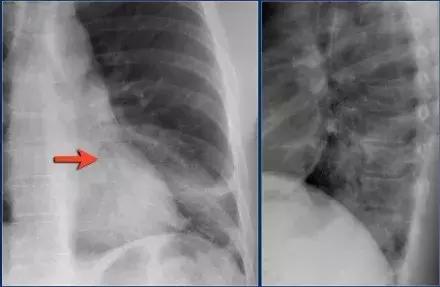

(1)影像一

图3 典型大叶实变

影像学表现:

➢ 左下肺边界模糊的密度增加的阴影

➢ 依然可见心脏轮廓,阴影出现在下叶

➢ 空气-支气管征

➢大叶性实变始于外周,由肺泡孔氏孔扩散

➢边界实变,由于一些肺泡参与实变,一些肺泡没有涉及,造成边缘模糊➢当病变发展到叶间裂,形成尖锐的轮廓,实变不能越过叶间裂

➢支气管周围肺泡更加密集,所以支气管相对更加明显可见,形成空气-支气管征(箭头所示)

➢肺实变时,肺体积应该没有或仅有轻微缩减。与肺不张有明显的不同

➢一般实变不会引起肺体积增大,但可见于克雷伯杆菌,时见于肺炎链球菌、TB和肺癌伴阻塞性肺炎